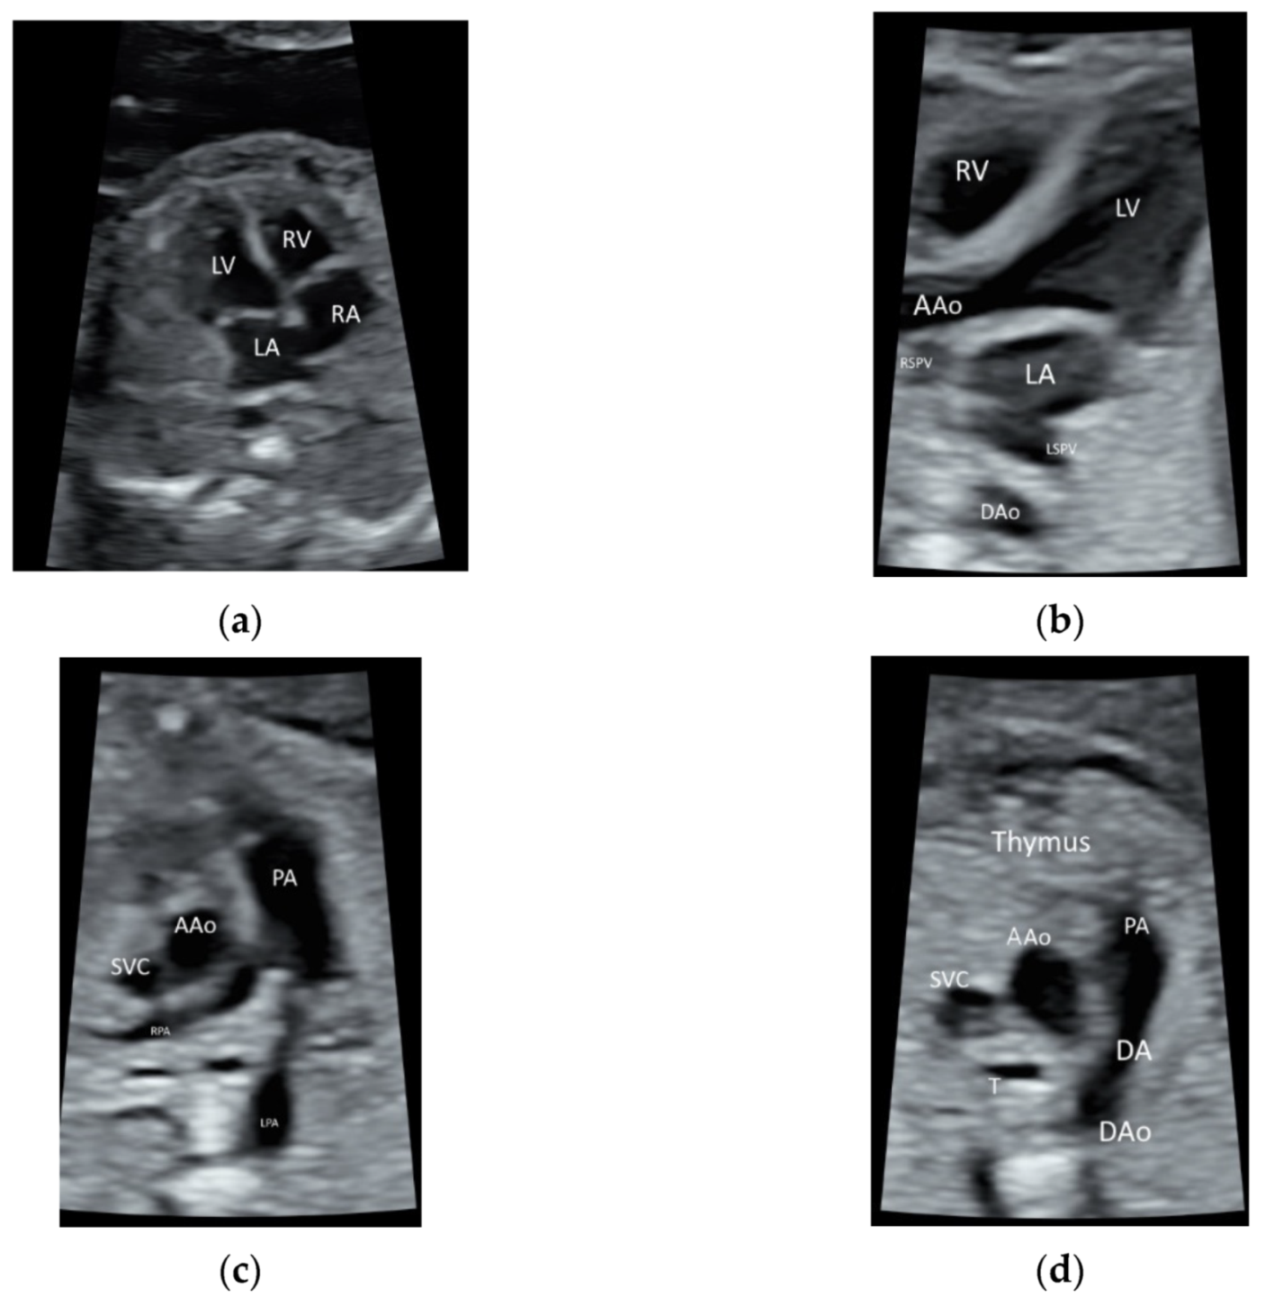

ISUOG recommends the use of the highest possible transducer frequency to perform fetal echocardiography with a view to improve the likelihood of detecting subtle heart defects, albeit at the expense of reduced acoustic penetration [10] (Figure 1a–d and Video S1). The use of HI can improve the quality of ultrasound images, especially when the maternal abdominal wall is thick during the third trimester of pregnancy [11,13].

Figure 1.

High-resolution ultrasonography of the fetal heart at 20 weeks’ gestation showing (a) a four-chamber view showing right atrium (RA), left atrium (LA), right ventricle (RV), and left ventricle (LV), (b) five-chamber view showing ascending aorta (AAo) arising from the left ventricle, the right and left superior pulmonary veins (RSPV, LSPV) enter the left atrium (LA), and descending aorta (DAo) behind the LA (c) Three-vessel view showing the PA dividing into the left (LPA) and right (RPA) PA, AAo, and the superior vena cava (SVC), (d) three-vessel and trachea view showing PA with the ductal branch (DA) joining the DAo, AAo, SVC, and trachea (T); Thymus is anterior to the three vessels.